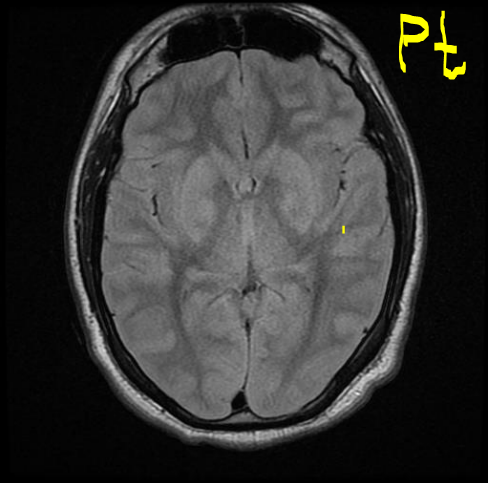

Case 4 Q# 1 of 4

• A 57 y/o man develops sudden left sided weakness while roller skating with his kids.

• Hx: he stopped taking his BP meds two weeks ago because they made him “feel weird.”

• Vitals : BP- 190/120, HR- 60, RR -12

• He has severe left sided weakness in his face, arm, and leg.

• The rest of his exam is normal.

• His MRI is attached.

What type of MRI is in the left image? The right image?

Left: T2W1 MRI. Right: DWI MRI.

Where in the brain is this man’s lesion located?

Within the right pons - the lesion has interrupted the tightly-packed fibers that are on their way to the brain’s motor cortex.

Given the location of the lesion, what type of blood vessel was likely involved? What was the pathogenesis behind the injury?

Lacunar (penetrating vessel) stroke. The ischemia was preceeded by hyaline arteriosclerosis.